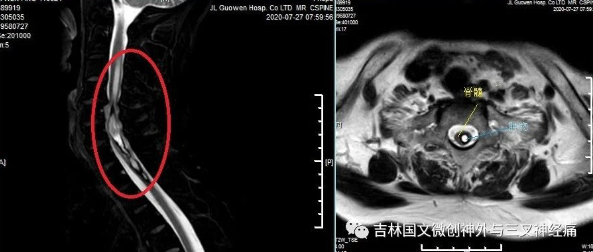

大娘姓李,62歲,家住梨樹縣。入院前約2年出現(xiàn)頸背部麻木感,當(dāng)時(shí)未在意,約1年前進(jìn)展為全身麻木感伴左側(cè)肢體運(yùn)動(dòng)欠靈敏。半年前于公主嶺**醫(yī)院檢查考慮為“脊髓內(nèi)占位”,家屬救治心切,輾轉(zhuǎn)四平及長(zhǎng)春多家大醫(yī)院,因考慮到各種因素猶豫不決,一直到患者行走困難,需要輪椅代步進(jìn)退兩難的境地時(shí),才得知吉大一院的羅毅男教授在我院出診,于是抱著試試看的心態(tài)來到。

羅毅男教授及王芃主任接診病人,表示腫物位于髓內(nèi),且部位較高,手術(shù)風(fēng)險(xiǎn)極大,極易導(dǎo)致高危截癱。向家屬詳細(xì)介紹病情,并以有限的資金完善術(shù)前相關(guān)檢查,明確無手術(shù)禁忌癥后,行手術(shù)治療。手術(shù)由羅毅男教授及王芃主任團(tuán)隊(duì)完成,歷時(shí)4時(shí)50分,手術(shù)順利完成,術(shù)后患者無明顯不適癥狀,四肢能動(dòng),活動(dòng)自如。